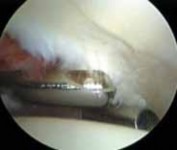

TECHNIQUES #### ARTHROSCOPIC REPAIR OF LESIONS OF THE LIGAMENTUM TERES AND PULVINAR

2. Disrupted fibers of the ligamentum teres, whether from trauma or degeneration, can be quite painful, creating soft tissue impingement within the joint.

3.

Associated with this soft tissue impingement, the pulvinar tissue often is hyperplastic or fibrosed and also can create painful symptoms.

4.

Indiscriminate débridement of the ligamentum teres should be avoided and intact fibers preserved; however, débridement of the disrupted portion can be quite beneficial ( TECH FIG 4).

8.

Most of the contents of the acetabular fossa are best accessed from the anterior portal.

9.

However, a portion of the posterior contents often is best accessed with instrumentation introduced from the posterolateral portal.

10.

Between these two sites most pathologic processes can be accessed with combinations of straight, curved, and flexible instruments.

---

A B C TECH FIG 4 • A. Arthroscopic view from the anterolateral portal reveals disruption of the ligamentum teres (

). B. Débridement is begun with a synovial resector introduced from the anterior portal. C. The acetabular attachment of the ligamentum teres in the posterior aspect of the fossa is addressed from the posterolateral portal. (Reprinted with permission from Byrd JWT, Jones KS. Traumatic rupture of the ligamentum teres as a source of hip pain. Arthroscopy 2004;20:385–391.) PEARLS AND PITFALLS Patient selection Patient positioning Portal placement Avoid iatrogenic damage Avoid excessive labral resection Avoid advanced disease states